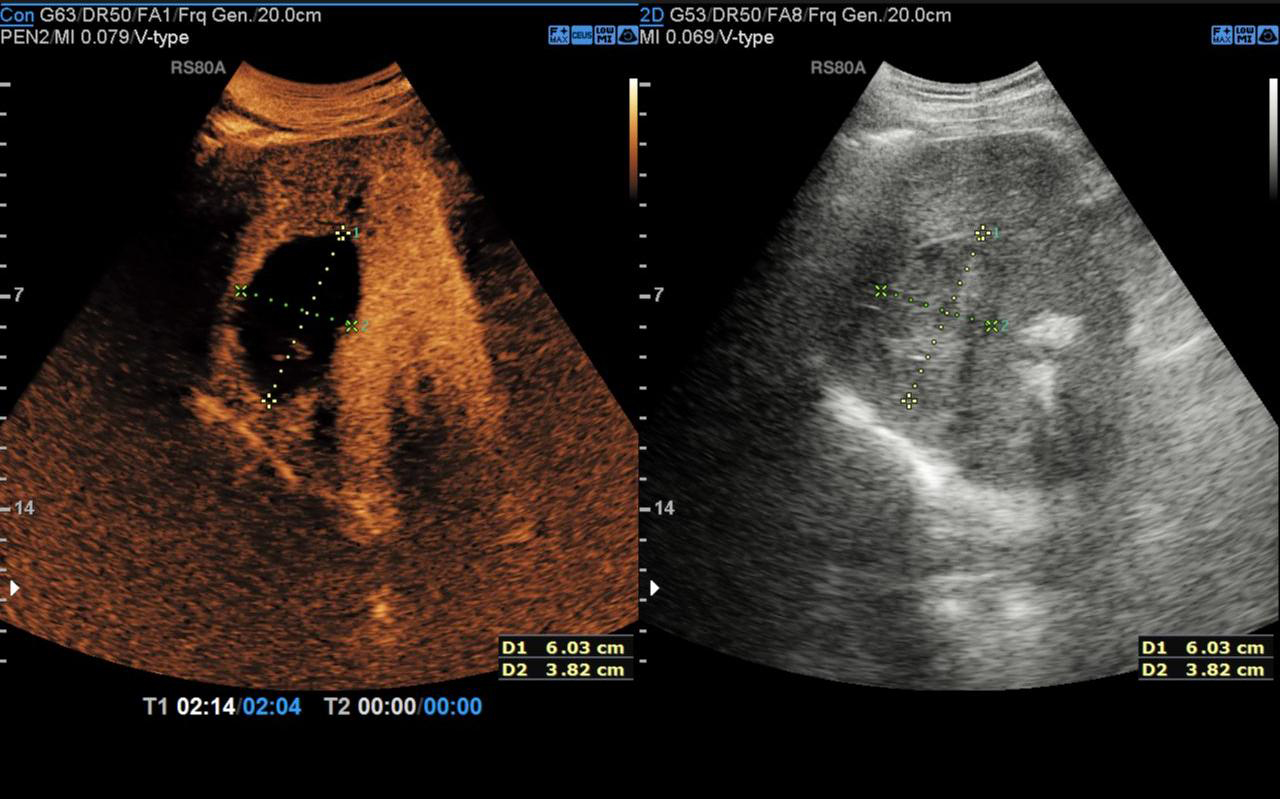

▲ 手术过程

消融完成后,术者退出电极针,经超声造影评估所有消融部位达到安全范围后手术顺利结束,术后给予对症支持治疗,患者恢复良好。术后3天超声造影显示肿瘤部位呈无血供现象,周边血管结构保存完整,消融效果良好且安全。术后1月超声造影显示病灶明显缩小,消融效果显著。